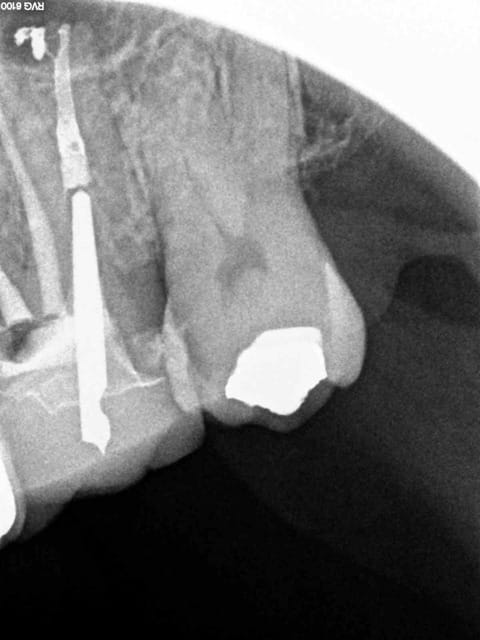

Le mv1 et le dv ont été obturés il y a 8 ans en mono cone.

En gutta chaude la différence se voit car ca n'est pas homogène à la radio comparé à un monocone scellé.

Marc vas jouer du mac spadden sur le canal palatin si ca te chante, mais pas sur moi ! -)))

4 wgbx1x - Eugenol

3 b4nxvh - Eugenol

1 phwbbp - Eugenol